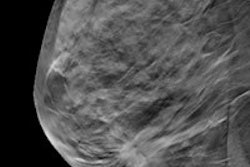

Density is calculated according to the percentage of fibrous and glandular tissue. Breast tissue with less than 25% density is categorized as fatty, 25% to 50% density is considered scattered, 51% to 75% is heterogeneous, and more than 75% is categorized as extremely dense, Perry said.

The study included 282 breast cancer cases and 317 healthy controls who had full-field digital mammography. Breast density was measured separately using an automated volumetric system, which generated a quantitative, reproducible density measurement.

"Assessing density is important, but we're not very good at it -- in fact, different radiologists may have only 60% agreement when classifying the two middle density grades," he said. "Using the automated system gave us an absolute measurement."

Breast cancer patients showed higher mammographic density than healthy participants up to the age of 50. The healthy controls demonstrated a decline in density with age that followed a linear pattern, while there was considerably more variability in density regression among the breast cancer patients, according to the researchers.